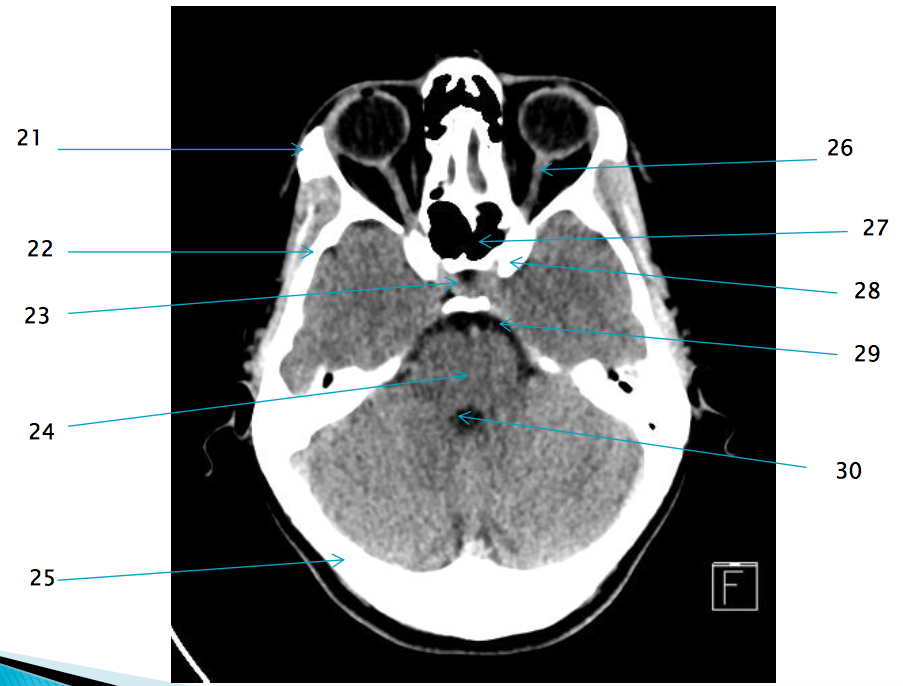

21

22

R temporal bone

29

28

L anterior clinoid process